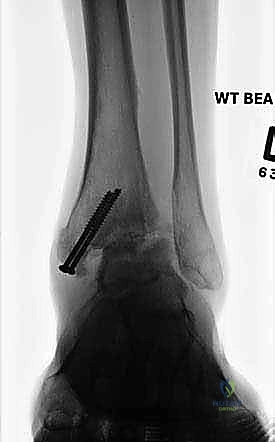

- الأشعة السينية أثناء الوقوف (Weight-bearing X-rays): هي الفحص الذهبي والأهم. يجب أن تؤخذ الأشعة والمريض واقف لتحمل الوزن. تظهر الأشعة تضيق المسافة المفصلية (دليل على فقدان الغضروف)، وجود نتوءات عظمية، تصلب العظم، وأي انحراف في محور المفصل.

| طرق العلاج | أدوية مضادة للالتهابات (NSAIDs)، أحذية طبية مخصصة (Rocker-bottom shoes)، دعامات الكاحل (AFO)، حقن الكورتيزون أو البلازما (PRP)، العلاج الطبيعي. | جراحة إزالة الغضاريف التالفة ودمج العظام (Arthrodesis) باستخدام مسامير وألواح معدنية. |

- التخطيط الجراحي الرقمي: باستخدام صور الأشعة المقطعية، يقوم الدكتور هطيف بتخطيط الجراحة على الكمبيوتر لاختيار حجم المسامير والشرائح المناسبة بدقة مليمترية.